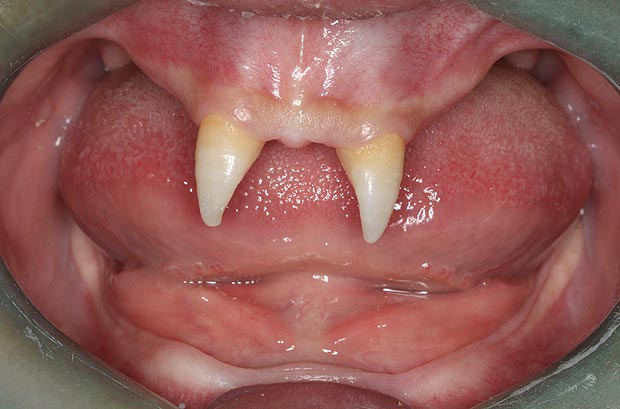

Վամպիրն ատամնաբուժարանում (լուսանկարներ)

16-ամյա մայրը Վանգ Պենգֆեյին բոլորը վամպիրի են նմանեցնում։ Տղան ընդամենը երկու սուր ժանիք ունի։

Պատանում մայրը՝ Վանգ Հույը, որդուն նախորդ շաբաթ նրան տարել է հիվանդանոց, որպեսզի պարզի այդ տարօրինակ երևույթի պատճառը և տղային նորմալի տեսքի բերեն։ Պատճառները պարզելու հարցում հույսեր կարծես չկան. բժիշկները դա համարում են բնական արատ։ Ինչ վերաբերում է այն շտկելուն, ապա դա հնարավոր է վիրահատության միջոցով։ Սակայն բժիշկները վիրահատությունը կկատարվի այն ժամանակ, երբ տղան չափահաս կդառնա։